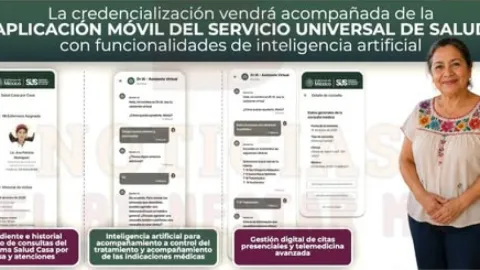

México Lanza Servicio Universal de Salud Digital: App MX Centraliza Expediente Clínico, Citas y Teleconsultas para 2028

México Lanza Servicio Universal de Salud desde Enero 2027 con Credencial Única